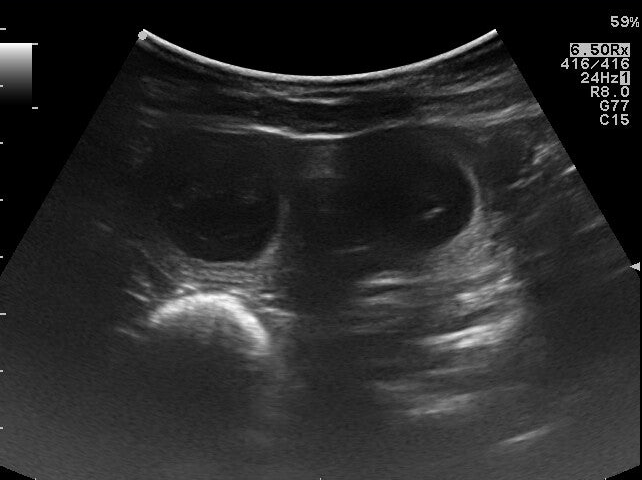

Wir freuen uns sehr, Elly ist trächtig. Wir konnten im Ultraschall viele kleine Herzen schlagen sehen. Immer wieder ein wahnsinnig tolles Gefühl. Jetzt hoffen wir weiter auf eine komplikationsfreie Trächtigkeit und Geburt der kleinen Wunderbärchen.